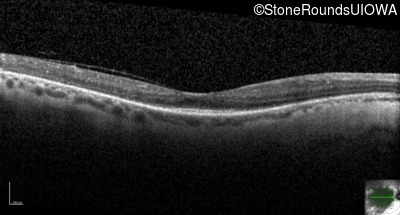

Optical Coherence Tomography - Right - 20/40 -2

Exemplar / OCT Stack

OCT Stack